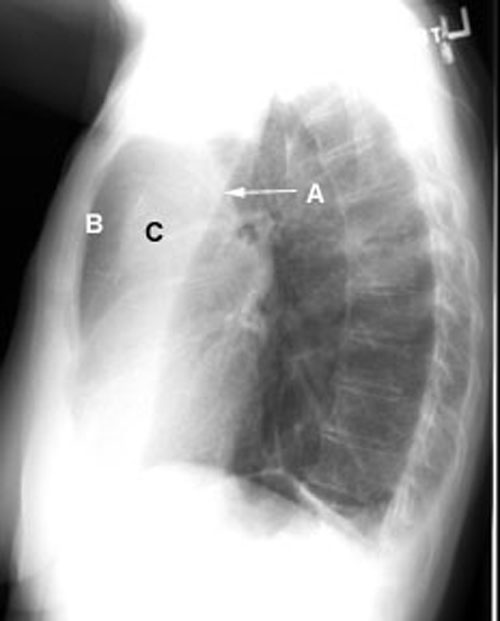

96a1.JPG (11184 bytes) Bowing Sign

In LUL atelectasis or following resection, the oblique fissure bows forwards in the lateral view. Bowing sign refers to this feature. (A) Forward movement of left oblique fissure (C) Atelectatic LUL (B) Herniated lung from right.